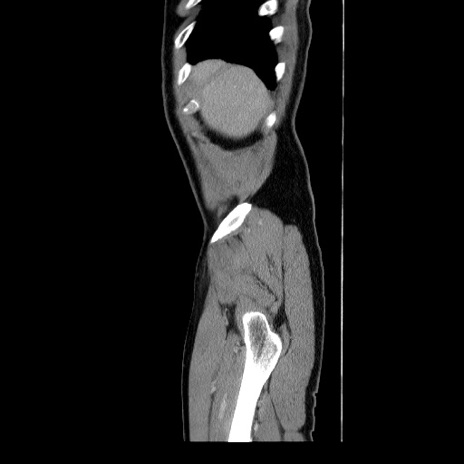

症例34(矢状断像)

【症例】60歳代 男性

【主訴】右鼠径部膨隆

【現病歴】1年程前より右鼠径部膨隆あり。自己にて還納可能だったため放置していた。3時間前より右鼠径部の脱出を認め、還納困難となり受診。

【身体所見】右鼠径部に小児頭大の膨隆あり。弾性硬であり、用手還納は困難。左鼠径部にも膨隆を認める。脱出はなし。